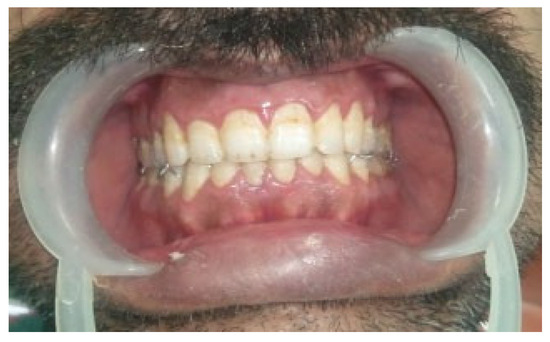

The management of atrophic mandibular fractures in edentulous patients represents an insidious issue for the maxillofacial surgeon due to the biological and biomechanical conditions that are unfavorable for fracture fixation and bone healing. The pur...